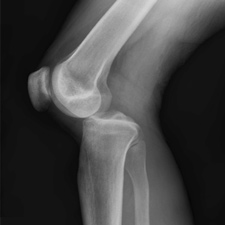

Коленный сустав является наиболее крупным и соединяет три части: большеберцовую кость, бедренную, а также коленную чашечку. Бедренная относится к бедру, большеберцовая вместе с малоберцовой образует голень, а коленная чашечка представляет собой кость овальной формы и призвана защищать сустав.

Когда пострадавший поступит в больницу, ему назначат некоторые диагностические процедуры, которые позволят оценить особенности травмы и степень её тяжести. Так, будет назначен рентген, чтобы выяснить, все ли кости целы. Необходимо измерение пульса, которое позволит выяснить, не нарушено ли кровообращение. Артериография (или допплерография) позволяет оценить состояние и целостность артерий. Такие процедуры назначаются, если есть подозрения на разрывы крупных сосудов (не прощупывается пульс, нога посинела).